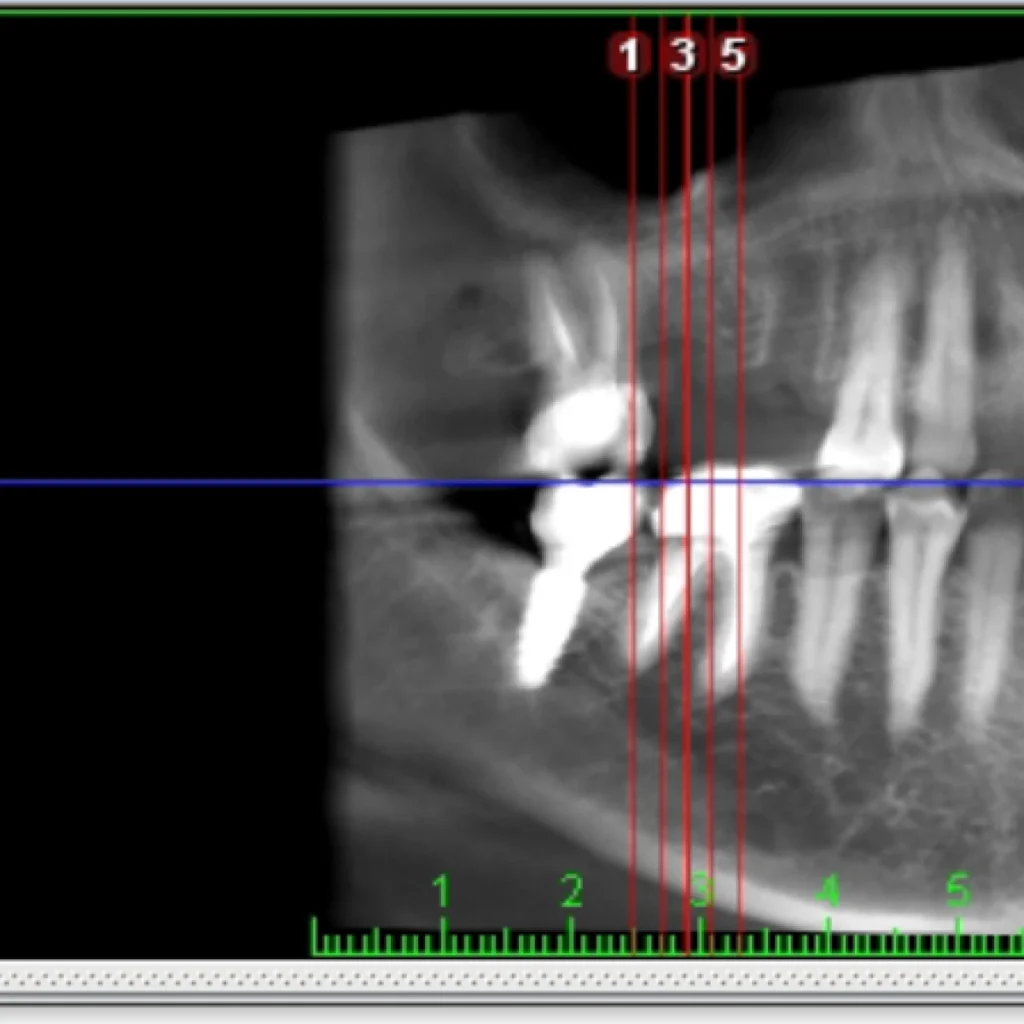

Un cone beam (équivalent d’un scanner) est réalisé sur place afin de valider le diagnostique et de vous proposer le traitement adapté à votre situation. Certaines font intervenir des biomatériaux (os de banque d’origine humaine ou animale; os de synthèse; os autogène prélevé directement dans votre bouche lors de l’intervention).

- Le scanner réalisé au cabinet met en évidence un défaut osseux majeur nécessitant une greffe osseuse complexe pour réhabiliter la zone par 2 implants.